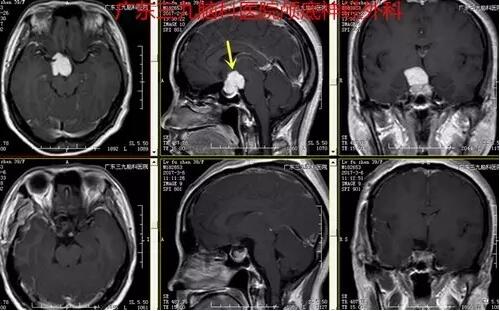

图2:术前磁共振提示鞍区及鞍上一形态不规则异常信号,增强后明显强化,范围约42.5pxx50pxx75px,颈内动脉海绵窦段受包绕

图4:术后磁共振提示肿瘤全切